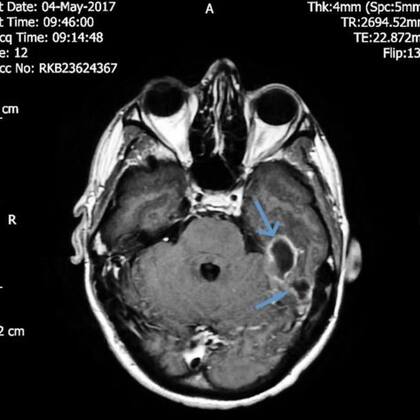

Cuando llegó al hospital, los médicos le hicieron una tomografía y las imágenes revelaron dos abscesos, o áreas inflamadas llenas de pus, en los huesos en la base de su cráneo, cerca de su conducto auditivo izquierdo. Esto indicó a los médicos que aunque la infección pudo haber comenzado dentro del canal auditivo del hombre, se había extendido más allá.